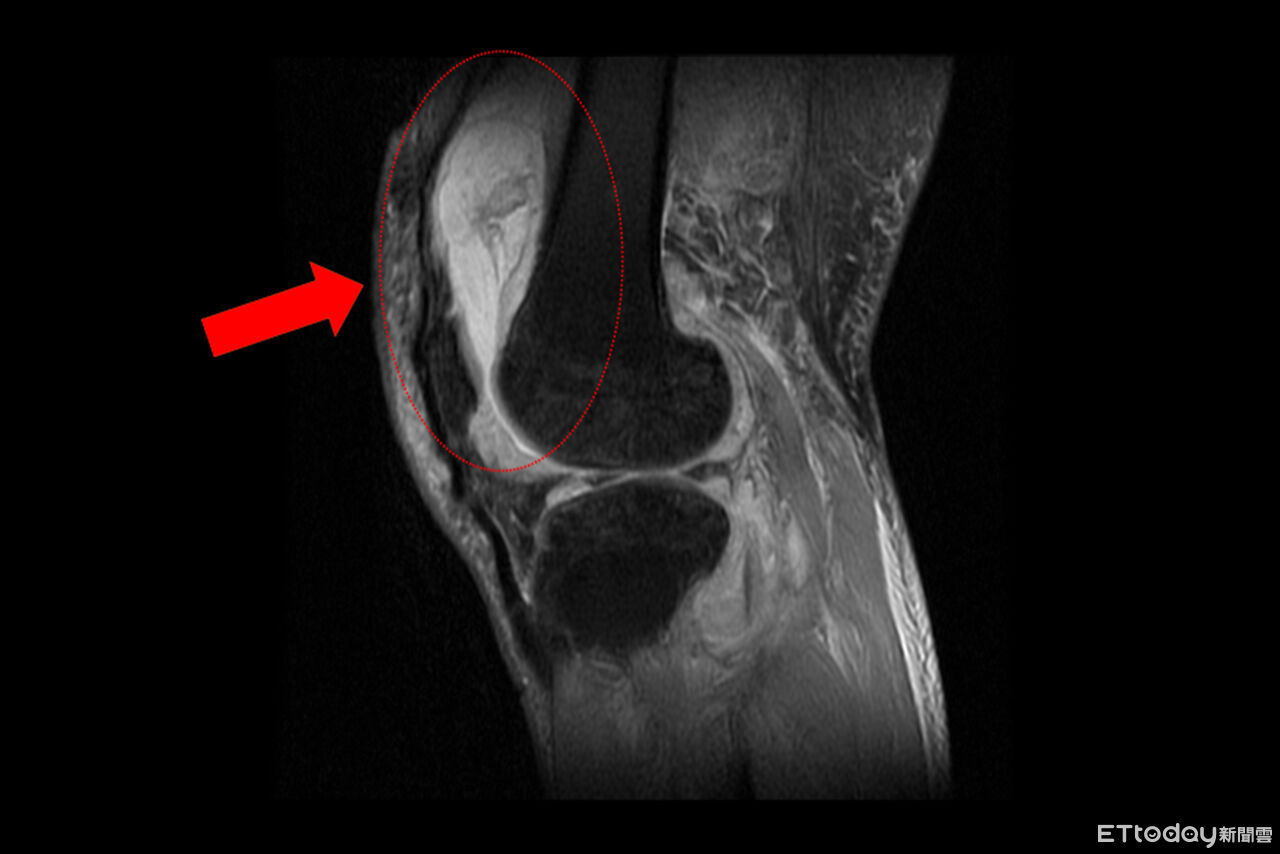

▲一名患者膝關節疼痛,竟是「肺外結核感染」。(圖/院方提供,下同)

台中慈濟醫院關節中心主任周立展指出,該患者長期左膝腫痛、幾乎無法行走,以為只是退化性關節炎,服用止痛藥、抽關節積水、熱敷復健,但卻越來越嚴重,就醫時膝蓋已腫脹無法彎曲,化驗後發現白血球數值雖偏高,但並非典型的細菌感染,懷疑有其他原因,進一步X光與磁振造影檢查,顯示膝蓋內已有大量積液並化膿,屬於嚴重關節感染。

周立展說,緊急施行微創關節鏡清創手術,檢體送病理化驗後竟發現結核分枝桿菌,顯示並非單純膝蓋退化,會診感染科與胸腔科醫師共同診斷,在病人痰液培養出結核菌,證實為「肺結核合併肺外感染」,結核菌最初在肺部引起感染,再經由血液或淋巴傳播,最後侵犯膝關節。